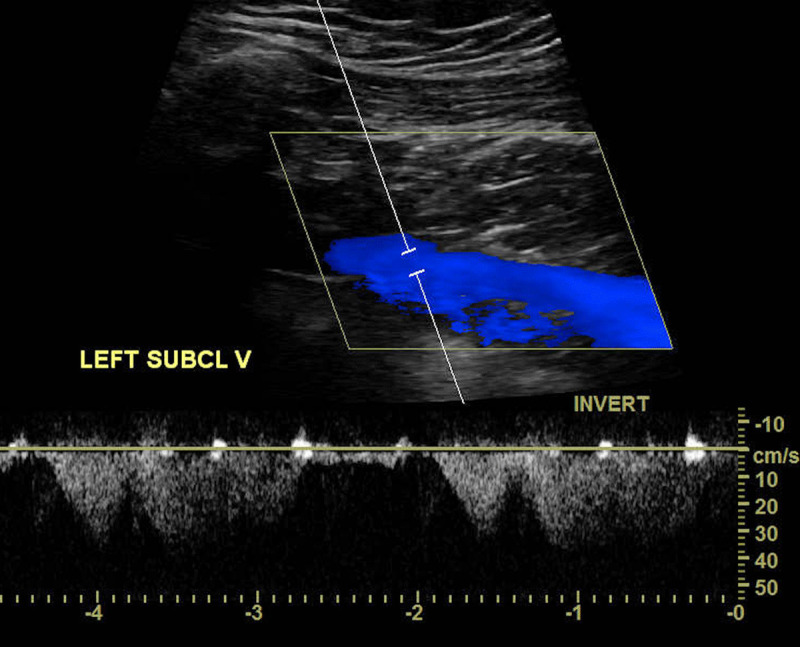

Fat emboli may occur in patients after traumatic fractures or orthopedic procedures; however, their clinical detection is a very rare finding. Here, we describe a 77-year-old female who was admitted to the emergency department with a fracture of the right humerus. We diagnosed fat embolism after an ultrasound of the right subclavian vein. The embolism was detected by high-intensity transient signals present on the spectral Doppler. While these signals are well known for microembolization in transcranial Doppler, to our knowledge this is the first case report in the medical literature to observe and describe high-intensity transient signals seen in the upper extremities by spectral Doppler. Although it is unusual to detect a fat embolism in transit, we believe clinicians should be aware of this finding, particularly when evaluating high-risk patients.